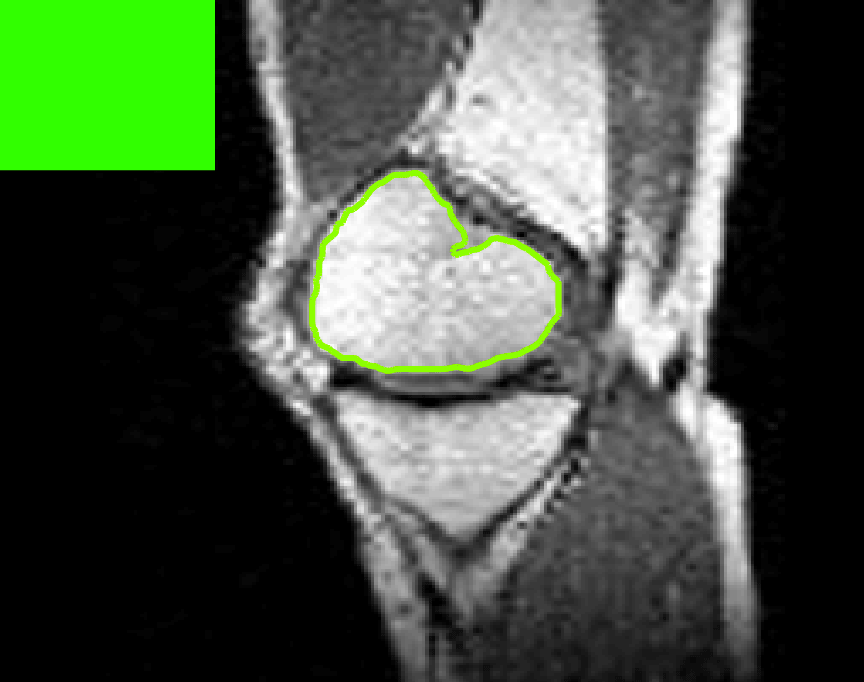

The motivation for this work comes from observing contradictions in using piecewise-constant intensity fitting terms in selective segmentation. Whilst good results are possible with this approach, the exceptional cases lead to severe limitations in practice. This is quite common in medical imaging as demonstrated in Fig. 1, where the target foreground has a low intensity. Given that the corresponding background includes large regions of low intensity, the optimal average intensities for this segmentation problem are and . For cases where , we see that by (1), almost everywhere in the domain . This means that it is very difficult to achieve an adequate result, without an over-reliance on the user input or parameter selection.

for and as defined in (33). This is consistent with respect to the intensities of the observed object and the concept of selective segmentation. In Fig. 3 we see the difference between CV and the proposed fitting terms for given user input on a CT image. For the CT image, the CV fitting terms are near 0 within the target region. This is despite there being a distinct homogeneous area with good contrast on the boundary. This illustrates the problem we are aiming to overcome. With the proposed fitting term this phenomenon should be avoided in cases like this. By defining as in (33) there is no contradiction if the foreground and background intensities of the target region are similar.

Test Images. We will perform initial tests on the images shown in Figs. 5–7. We have provided the ground truth and initialisation used for each image. Test Images 1–3 are synthetic, Test Image 4 is an MRI scan of a knee, Test Images 5–6 are abdominal CT scans, and Test Images 7–9 are lung CT scans. They have been selected to present challenges relevant to the discussion in §2. We focus on medical images as this is the application of most interest to our work. In the following we will discuss the results in terms of synthetic images (1–3) and real images (4–9). We also test the proposed approach on a larger data set of 30 CT images (a sample of which is presented in Fig. 18), comparing against existing selective methods detailed in §3.

Real Images. In Fig 12 we present results for Test Images 4–6. Here, the proposed model performs in a similar way to its competitors because these images are more typical selective segmentation problems in the sense that there is a clear distinction between the foreground and background intensities. In particular, the values in each case are: Test Image 4 , Test Image 5 , and Test Image 6 . It can be seen that the proposed model is competitive compared to previous approaches. The performance is quite poor for Test Image 5, but is arguably still the best for this challenging case. In Fig. 13 we present results for Test Images 7–9. Here the proposed model outperforms previous approaches significantly for each image. This is mainly due to the type of image considered. Specifically, the true intensities are: Test Image 7 , Test Image 8 , and Test Image 9 . The proposed model is capable of achieving results where , with other models failing completely in these cases.

Real Images. In Table 1 we can see that the proposed model is the most successful in terms of optimal accuracy. It is worth noting some inconsistency in the other models, with all but GAV having results that fall below TC for at least one image. GAV performs well for Test Images 4–9, with the proposed model slightly outperforming it in each case. It is worth reminding the reader that for GAV the parameters have been refined for each example. Fixing this results in more variability in the quality of results. The proposed model has no such parameter optimisation between examples. CAC and SRW perform reasonably well for these images, although are sometimes substandard for Test Images 4-7. This is despite extensive refinement of the user input to achieve an acceptable result. We present the optimal results for Test Image 9 in Fig. 14. Here we can see how much variation there is in the quality of results for this lung CT image. CAC and SRW are competitive in this instance. Of the remaining approaches GAV is the most competitive (TC ), but is visually inadequate. Two other models (CV, HYB) fail completely. In this case, the problem looks quite straightforward and yet other fitting terms are insufficient to produce a good result. Again, the proposed model tends to be superior in cases where and is capable of achieving very good results for all the images considered. This highlight the advantages of the proposed fitting term.